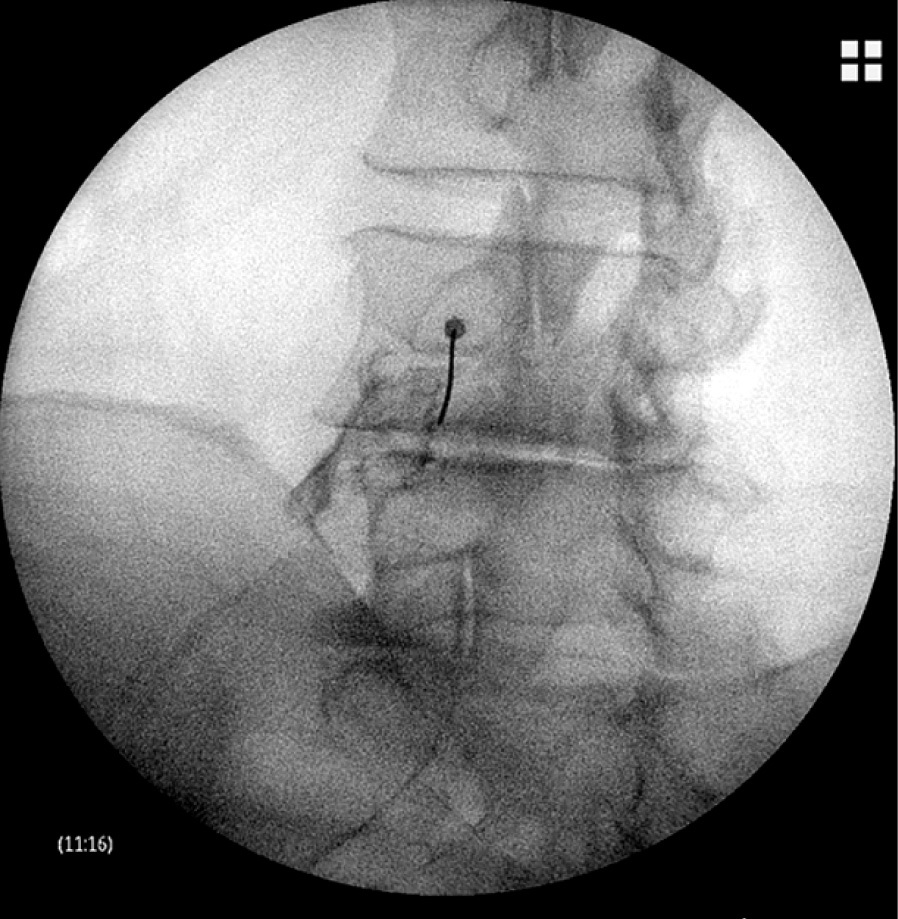

Методика интерламинарного введения

На поясничном уровне; положение пациента – лежа на животе с валиками или подушками, расположенными так, чтобы оптимально увеличить пространство между остистыми отростками и дужками позвонков. Под контролем флюороскопа выводится на экран передне-задняя проекция (anterior-posterior, AP) для идентификации целевого уровня пункции. Для улучшения визуализации межостистого интервала используется наклон флюороскопа в каудальном или головном направлении по оси тела пациента, а косой угол от 5 до 15º используется для визуализации траектории для парамедиального подхода. После обезболивания кожи местным анестетиком в проекции межостного промежутка вводится эпидуральная игла Туохи. Игла вводится послойно до появления сопротивления жёлтой связки, тогда стилет удаляют, к игле присоединяют шприц низкого сопротивления, наполненный физиологическим раствором.

Эпидуральное пространство идентифицируется методом «потери сопротивления». Для верификации положения иглы в эпидуральное пространство в небольшом количестве вводится контрастное вещество, после чего на флюороскопе в AP проекции следует наблюдать асимметричное, вакуолизированное контрастное распространение, соответствующее эпидуральному пространству [4]. Если глубина введённой иглы недостаточная, то на рентгене может наблюдаться плотное пятно, в этом случае игла должна быть продвинута дальше. Быстро рассеивающийся сосудистый рисунок подразумевает внутрисосудистую инъекцию, и размещение должно быть скорректировано. Если игла была введена слишком глубоко, может наблюдаться симметричный, гладкий и слабый рисунок, указывающий на субдуральную инъекцию. В этом случае врач-клиницист должен вывести иглу и выбрать альтернативный уровень пункции.

В нашей клинике при выполнении ИЛ инъекции на шейном уровне также применяется подход с положением пациента лежа на животе. В данных литературных источников, положение лежа позволяет приблизиться к уровню C7-Th1, несмотря на плечи, которые наслаиваются на флюороскопической картинке в боковом положении дуги флюороскопа (рис. 1). Использование техники «висячей капли», по данным различных авторов, в этом положении не подходит из-за положительного давления, создающегося в эпидуральном пространстве на шейном уровне позвоночника [5]. Наши же наблюдения показывают метод «висячей капли» эффективным для идентификации эпидурального пространства. По наблюдениям нашего центра, при попадании кончика иглы в эпидуральное пространство, при наличии раствора контрастного вещества в павильоне иглы, капля втягивается внутрь отрицательным давлением в эпидуральном пространстве в большинстве случаев (табл. 1).

Рис. 1. Интерламинарная эпидуральная инъекция с типичным распространением контрастного вещества / Fig. 1. Interlaminar epidural injection with typical contrast agent spread